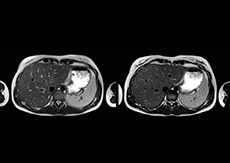

“We also love MultiVane XD for motion reduction in imaging. We find this a huge step forward. We use it in the head, and of course in the upper abdomen, and the images are outstanding most of the time. And it can be combined with dS SENSE parallel imaging for speed.” “We have compared image quality of FLAIR with MultiVane XD versus FLAIR without MultiVane XD. In 15 of the 40 patients studied, we saw motion artifacts on plain FLAIR brain images. The FLAIR images with MultiVane XD were motion-free in 39 of 40 patients and showed slight motion artifacts in only one patient.”

“In our lumbar spine MRI, the value of mDIXON TSE is so obvious. Normally we perform T1 and T2 scans in sagittal and transverse orientation.It used to take too much time to add a sagittal T2 with good fat suppression.But now, using mDIXON TSE, we get the sagittal T2 fat suppressed images ‘for free’, that is: without adding time.” “Diagnostically that is a great benefit. I sometimes see abnormalities in the fat suppressed sagittal T2 that would be quite challenging to notice in the T2 without fat suppression. There have been several diagnoses that I could make easier because of our exam setup with mDIXON TSE, such as sacrum insufficiency fractures and sacroileitis; these were more challenging with our previous exam setup.”